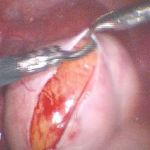

2008年9月20日安太医院腹腔镜探查:左卵巢囊肿,直径7cm,暗紫色,与左侧输卵管、左侧盆壁、肠管、大网膜结缔组织性粘连,操作:腹腔镜下穿刺左卵巢囊肿,抽出囊内液20ml送细胞学检查,液体为血性。松解左输卵管、卵巢与周围组织的粘连。细胞学检查结果回报为白细胞、红细胞,未见肿瘤细胞。完整剥除囊肿壁,囊肿壁为黄体组织,考虑左卵巢囊肿为黄体囊肿合并出血,3-0可吸收线连续缝合左卵巢成形。

术后诊断:卵泡黄素化不破裂综合征(LUF)

讨论:术前根据年龄和生长速度高度怀疑卵巢癌,术中确是卵泡黄素化不破裂综合征,这个现象在更年期妇女尤其明显,卵巢肿物虽然大于7cm,B超虽然提示囊实相间,仍是生理性的囊肿,实性部分就是血体。可以通过介入治疗的。